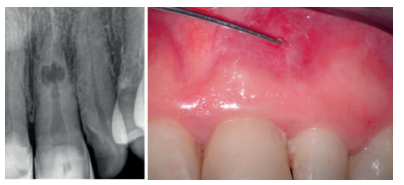

Nos refieren a la consulta una mujer de 60 años, sin antecedentes médicos de interés, que sufrió un traumatismo con anterioridad, aunque no recuerda la fecha con exactitud. Presenta ligeras molestias a nivel gingival y sostiene que sufrió episodios de inflamación y dolor. A la inspección intraoral presenta una fístula o trayecto sinusal a la altura del 21 y unas carillas de composite desgastadas en el sector antero-superior. Las pruebas diagnósticas realizadas sobre el diente 21 indican la ausencia de vitalidad y percusión vertical, palpación positiva y sondaje-movilidad fisiológica. Los dientes 11 y 22 se encontraban asintomáticos y con vitalidad positiva normal.

Tras realizar una radiografía periapical (Figura 1) se puede observar un ensanchamiento de forma ovalada a la altura del tercio medio del conducto del diente 21, que puede corresponderse con una reabsorción. Ante este hallazgo radiográfico, se decide realizar una prueba complementaria mediante CBCT (CS 8100, Carestream Dental, Atlanta, Estados Unidos) para comprobar la extensión de la lesión y si ésta es o no perforante.

Se realiza un CBCT de campo pequeño con un voxel de 75 micras. A través de las pruebas complementarias, estudio radiográfico y análisis de la literatura llegamos al diagnóstico de reabsorción interna inflamatoria perforante (Figura 2).

En la primera sesión, al realizar la apertura se detecta un tejido inflamatorio (Figura 3) procedente de la reabsorción interna, con lo que se procede a realizar irrigación con hipoclorito al 2,5 % (Dentaflux, Madrid, Spain) y colocación medicación intraconducto de hidróxido de calcio (Calcicur, Voco, Cuxhaven, Alemania) durante 7 días11 .